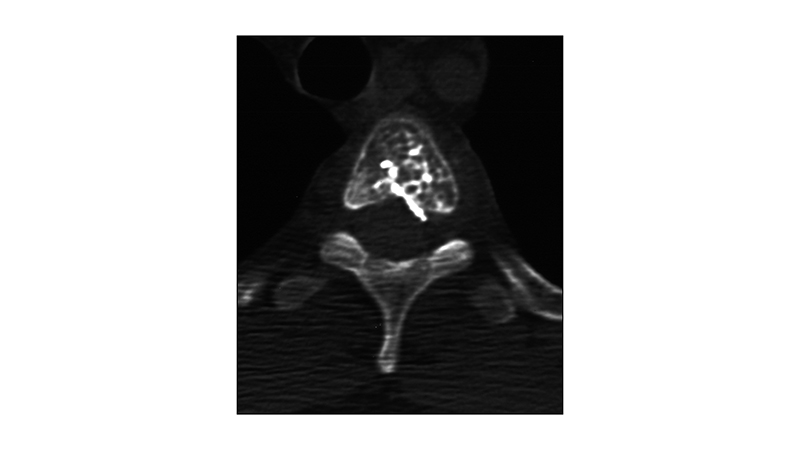

Εικόνα 7: Αξονική τομογραφία, στο επίπεδο του Θ3 μετά τον εμβολισμό: Διακρίνεται το εκμαγείο της κυανοακρυλικής κόλλας.

peristatiko aimaggeiwmatos spondulikhs sthlhs.007